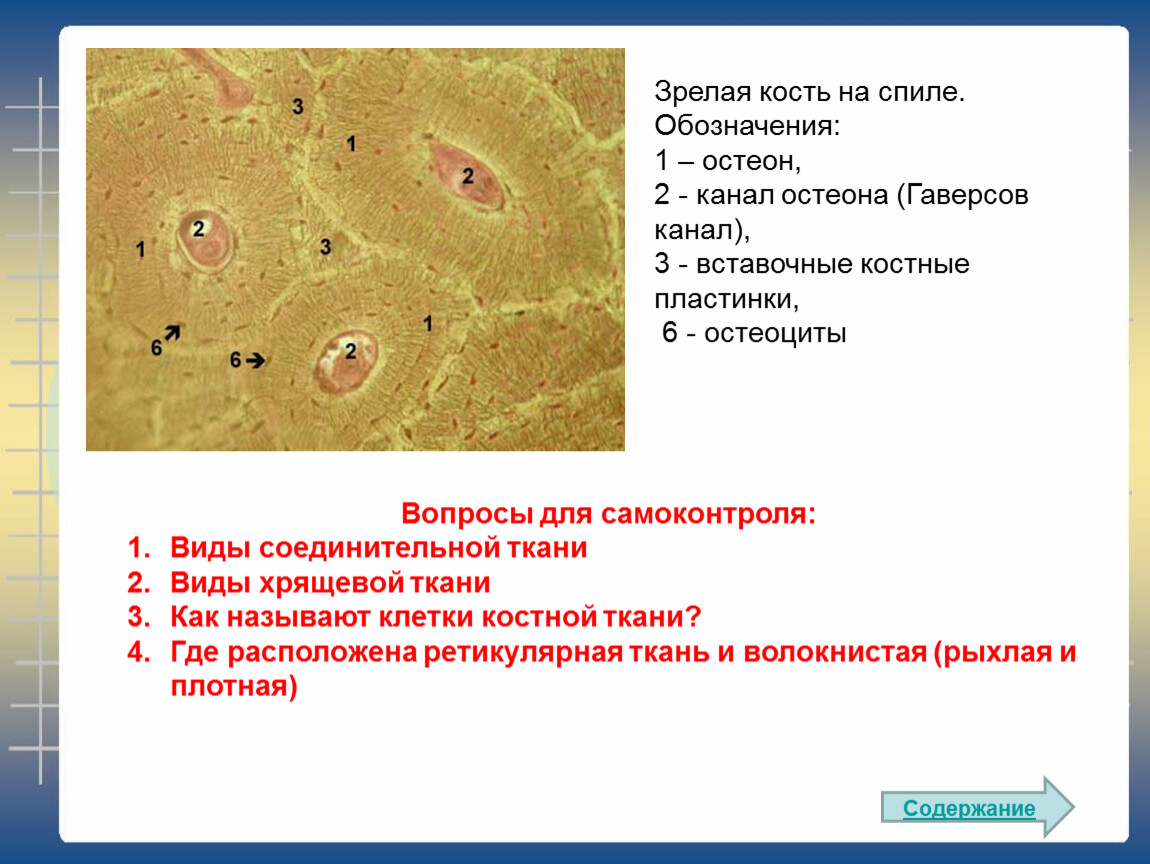

Структура грубоволокнистой костной ткани: наглядные примеры